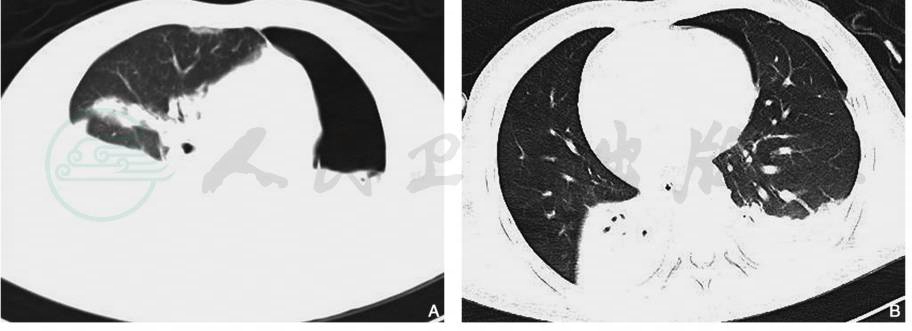

图4肺挫裂伤(磨玻璃气囊征)

男性,2岁,胸部CT平扫肺窗(A)显示右肺上叶斑片状高密度影及气体密度影,壁较厚,内可见多处分隔(箭);同层纵隔窗(B)显示右肺上叶含气囊腔的壁光滑,厚薄均匀

引自:中华影像医学·呼吸系统卷.第3版.ISBN:978-7-117-28903-0.主编: